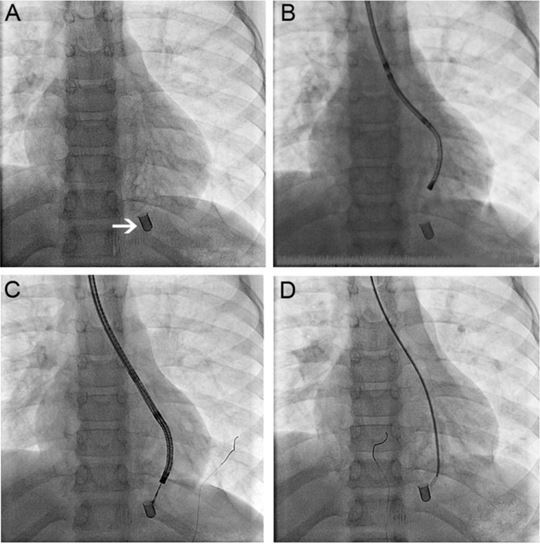

10 岁男孩因 2 个月来反复出现呼吸困难被收入呼吸科。胸片显示左下肺叶的后背段有异物存在(图 2 A)。在异物停留部位有支气管扩张的改变,说明有慢性炎症。鉴于异物所处的部位过深,单独应用肺部介入技术取出异物难度过大,便决定联合心脏介入技术进行治疗。

图 2 A 胸片显示异物在左下肺叶;B 纤维支气管镜靠近异物;C 通过纤支镜放入的活检钳不能夹取异物;D 透视下,指引导管可以深入到距离异物 1 到 2 mm 的部位 全麻并插入 6.5 mm 的支气管导管。将 2.8 mm 的支气管镜连接双轴旋转接头,在透视介导下,探查左主支气管直至不能深入。此时支气管镜距离异物仍有几毫米(图 2 B)。

之后,在透视介导下,我们将有齿活检钳(FB-56-D1, Olympus Optical Co, Ltd, Tokyo,Japan)通过 3.6 mm 的纤维支气管镜的吸引管放入,并多次尝试夹取异物,而没有成功,但是从异物周围吸引出了厚厚的、白色分泌物。

撤出纤维支气管镜后,将 4-Fr 的 Terumo 指引导管和 0.018 英寸的 Hi-Torque Flex-T 导丝通过旋转接头送入。在透视介导下,导管很容送到了异物周围(图 2 D)。之后将导管替换为 6-Fr JR-4 的大口径指引导管。

由于异物周围有一层由炎症分泌物和纤维组织构成的坚硬、有韧性的物质,多次尝试通过捕捞器以及血管钳取出异物都没有成功。无法让导管通过异物周围所包围的物质。透视结果显示,导管和活检钳距离异物只有 1 到 2 mm 远(图 2 D)。

此时注意到在支气管导管的远端以及指引导管上有少量的出血,认为继续取异物会有一定的风险,便用普通生理盐水清理了远端气道并吸引干净,以防止有未发现的出血。

之后,将捕捞器、指引导管和支气管导管取出。操作全过程中,除了最后出现少量出血外,没有出现其他并发症。透视时间一共为 45 分钟,计划之后对患者进行肺叶切除手术。